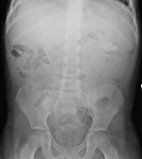

Persistent constipation is also prevalent in this population. As a result, almost a quarter of CF patients have experienced rectal prolapse. Prolapse is rarely the initial presentation of CF, so consider other diagnoses (ie, Hirschsprung disease) first in the absence of other symptoms. However, with recurrent prolapse associated with diarrhea, evaluation for CF is warranted.1 Constipation must be differentiated from DIOS, which can present with acute right lower quadrant pain and signs and symptoms of SBO (Figure).

Distal intestinal obstruction syndrome is most common in older adolescents with a prevalence of 10% to 15.8%.13 The greatest risk factor is prior DIOS. In constipation, stool and gas accumulate gradually in the colon with or without colonic dilatation. Nonstimulant laxatives (ie, polyethylene glycol) are most commonly used for treatment of constipation and prevention of DIOS. Patients may require admission for nasogastric administration of the large volumes that are often needed (20-40 mL/kg/h) until effluent is clear. A gastrografin enema can be performed by a radiologist for treatment of DIOS.

If DIOS is refractory to standard treatments, alternate diagnoses should be considered, such as intermittent intussusception, ileal Crohn disease, or appendicitis. In CF, appendicitis mimics DIOS due to its atypical presentation with classic symptoms frequently absent. Interestingly, appendicitis occurs in 1% to 2% of children with CF compared with 7% of the non-CF population, likely because of the frequent use of antibiotics in CF. However, due to confusion with DIOS, perforation is more common.12